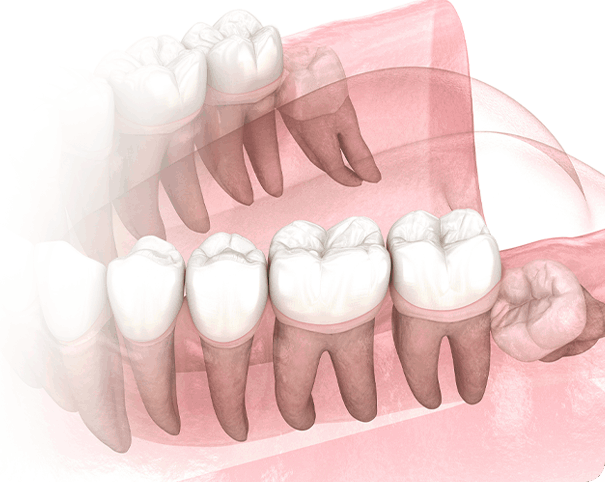

하지만 잇몸에 매복된 채 자라나는 사랑니는 구강관리가 어려워 인접 치아에 충치와 염증을 쉽게 불러일으킬 수 있습니다.

이를 방치할 경우 병변 부위가 넓어지면서 치료 비용과 기간이 높아지고 사랑니 뿌리와 잇몸뼈가

단단히 유착되어 발치하는 것이 매우 어려워 집니다.

잇몸과 뼈에 붙어있던 사랑니가 어금니를 흡수시켜 어금니를 사용할 수 없게 만듭니다.

수평으로 누운 매복사랑니는 바로 절단한 후에

남아있는 치아를 파절시켜서 제거합니다.